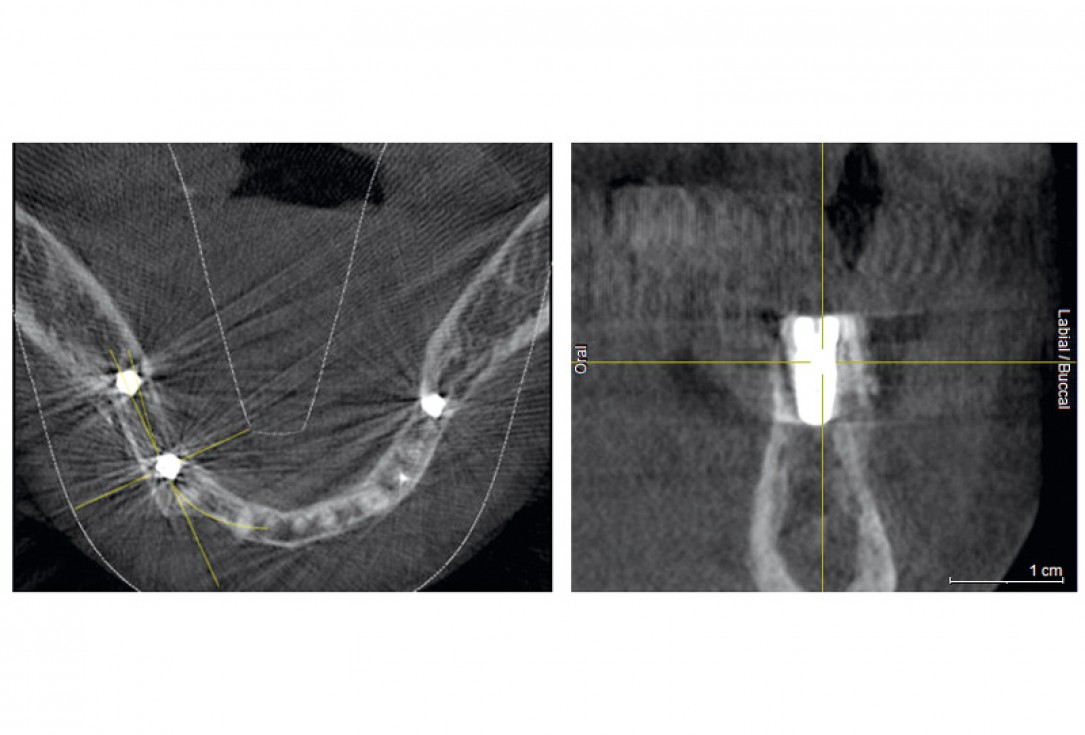

08 / 20 - CBCT recording after the augmentation shows the cortical plate about 3 to 4 mm distant from the host boneHorizontal ridge augmentation with maxgraft® cortico - M.Sc. E. Kapogianni

16 / 20 - CBCT after the implantation shows position of the implant within vital bone tissue and the adjacent allogenic cortical plateHorizontal ridge augmentation with maxgraft® cortico - M.Sc. E. Kapogianni